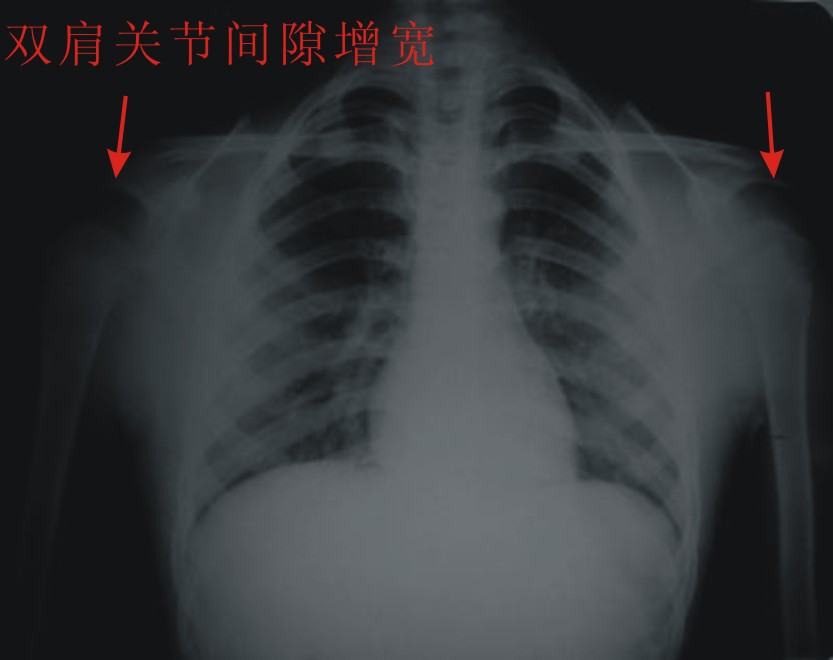

患者,男,13岁。自诉两月前双肩关节时有弹响,有时左、右肩关节轮换隐痛。但双上肢能抬举、左右旋转、屈伸自如。pe:双肩及双上肢皮肤无红、肿。触诊:双肩关节区域有抖动,似触心脏的搏动感,但抖动、搏动感能自控。双肩区域皮肤无发热。听诊:用耳贴近患者双肩区能听到弹响声。x线胸部后前位示:双肩关节间隙增宽,考虑双肩关节半脱位。双肩关节正侧位片示:双肩关节无明显脱位征象。双肩关节区域透视示:双肩关节解剖位时,双肩关节间隙增宽(与胸部后前位的双肩关节间隙相等),也能见双肱骨头在双肩关节腔内上、下移动约1cm左、右。但患者能自控(双肱骨头在双肩关节腔内不上、下移动)。请战友们详见患者相片、胸部后前位片、双肩关节正侧位片。我第一次碰到这样的病例(是否是神经性关节病“夏科氏关节”?),经验不足,希望能帮助诊断。亦请分析病因、病理机制,是什么原造成的?最好能提供治疗方法,谢谢!

双侧肩关节解剖位时,双肩关节间隙增宽,但肱骨头及周边骨质 关节腔均未见异常。与骨科专家会诊结果,目前只能诊断:肩关节松弛症!

双肩关节间隙增宽,但肱骨头及周边骨质 关节腔均未见异常。